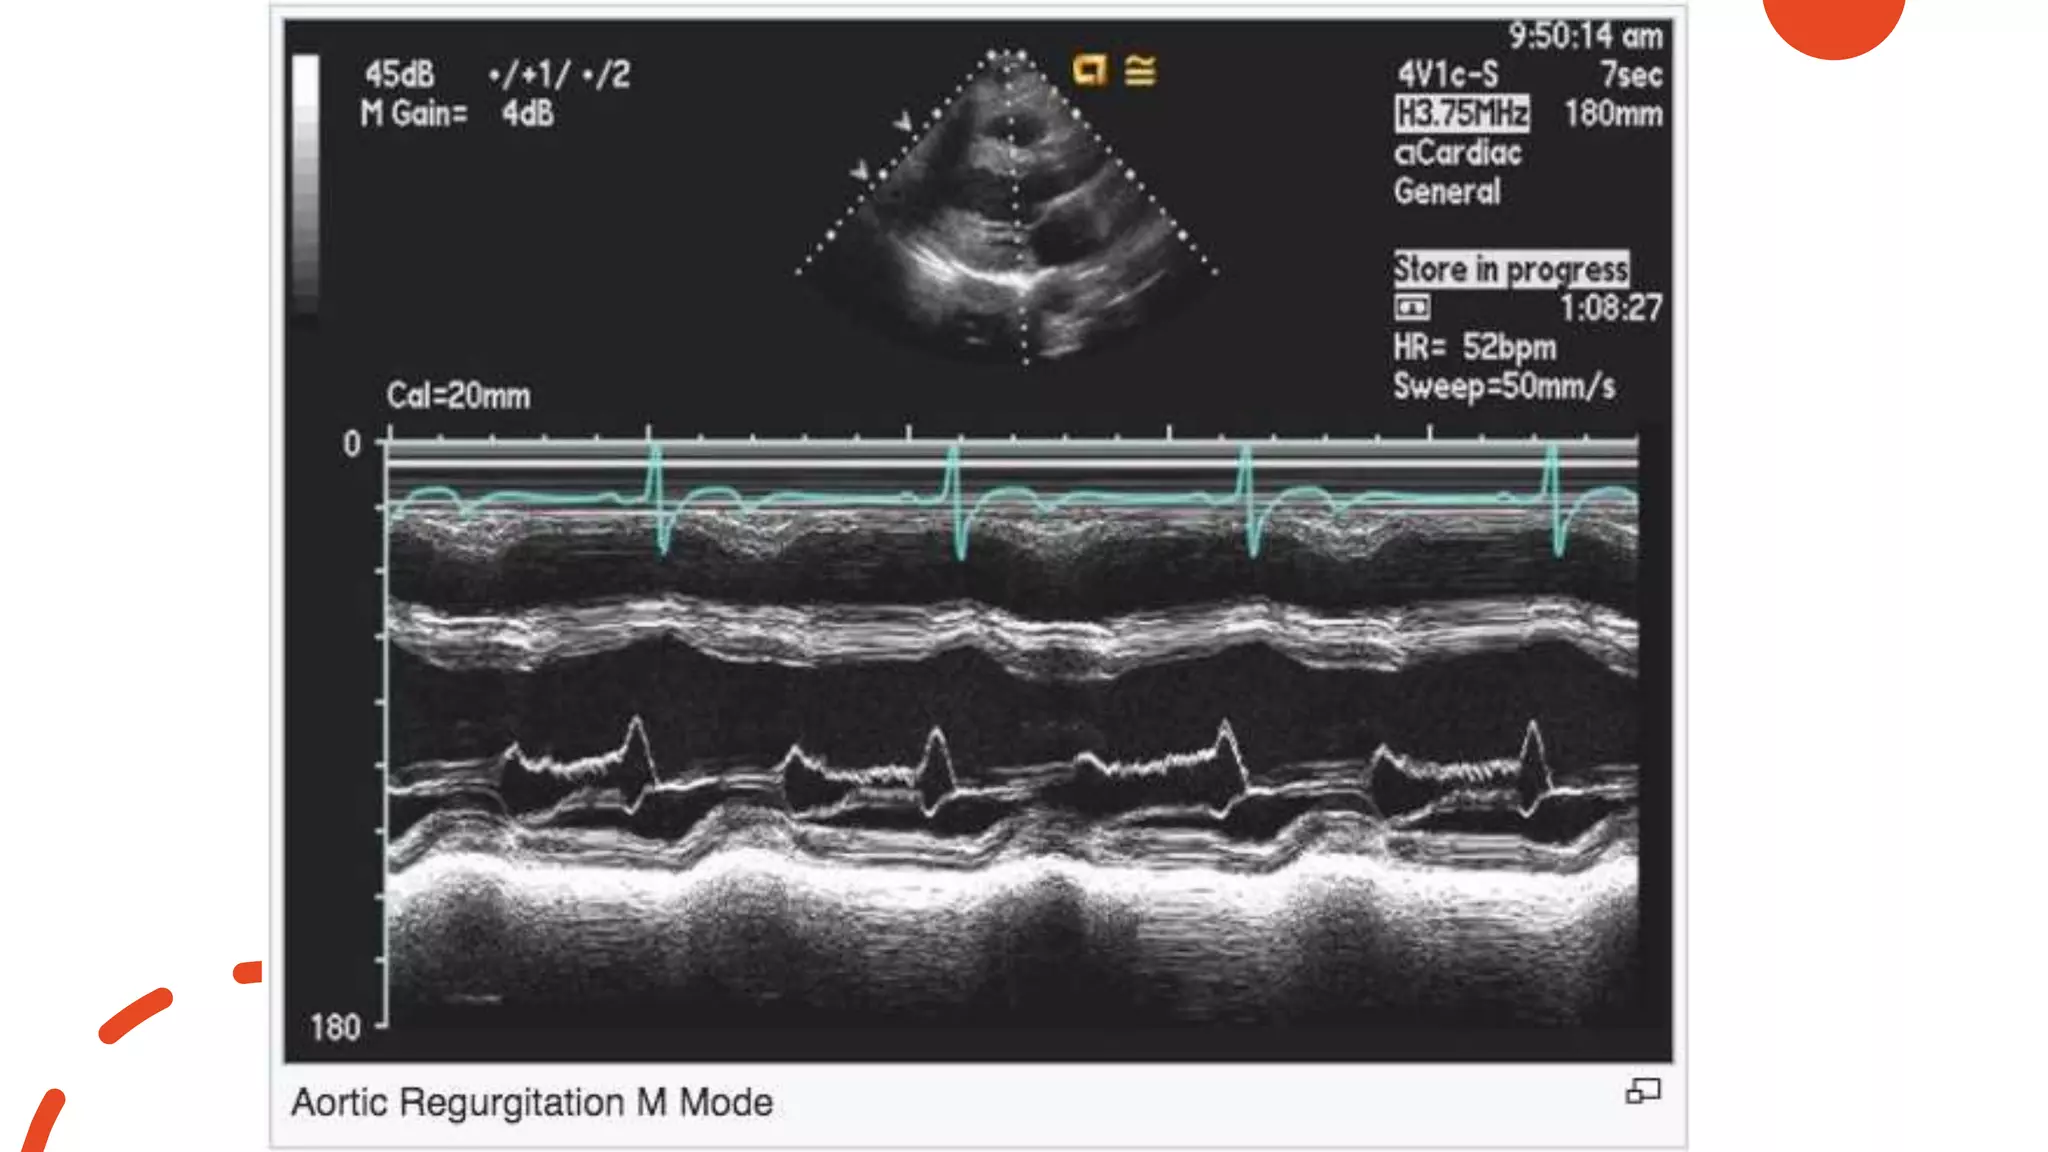

Aortic Regurgitation

• Diastolic fluttering of AMVL due

to AI jet turbulence

• Diastolic fluttering of aortic valve

• Premature closure of mitral valve

• Premature opening of aortic valve

• Dilated LV

• Increased duration between E

and A peaks

• #74 Figure 6 (A) Example of aortic regurgitation (AR) jet impinging on the anterior mitral valve leaflet with a reverse doming of the anterior mitral valve leaflet; (B) M-mode recording showing the fluttering motion of the anterior mitral leaflet in a patient with severe AR.